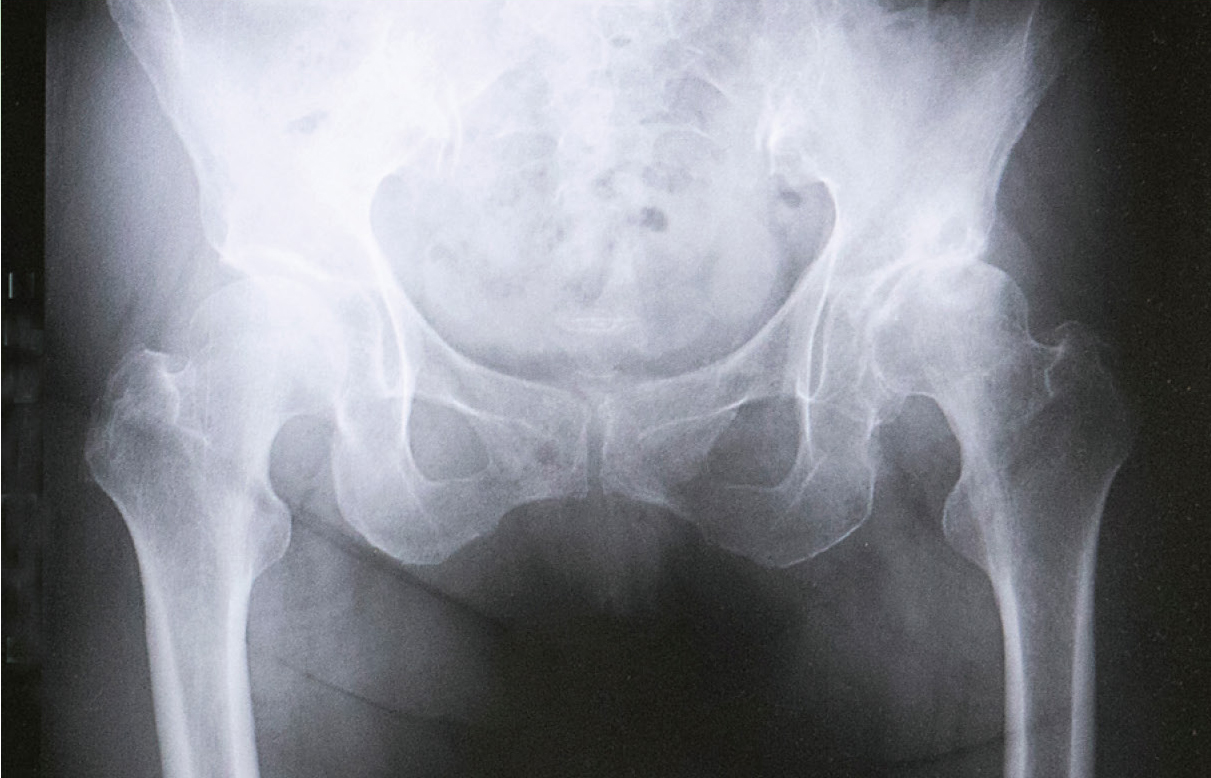

変形性股関節症のレントゲン

などで見つけられるものもあれば、画像診断でも判明しにくいものもあります。原因が骨や軟骨にある場合もあれば、股関節周囲の軟部組織(靭帯や筋肉、腱など骨以外の組織)に原因があるケースもあります。そのため、どこがどのように痛いのか、また痛みのためにどれくらい困っているかをしっかりと先生に伝え、診察を受けることが大切です。股関節の痛みで最も多いのが「変形性股関節症」です。股関節は、太ももの骨(大腿骨)の頭部にある骨頭とよばれるボール状の骨が、骨盤側のお椀の形をした寛骨臼(かんこつきゅう)にはまり込むような構造になっています。その屋根の部分の被りが浅い「寛骨臼形成不全」が「変形性股関節症」の約8割を占めます。被りが浅いので十分な支持力を保ちにくいため、関節唇という寛骨臼の被りを広げる役目をする部分に過度に負担がかかり、関節唇や軟骨がすり減って痛んでしまいます。原因は遺伝や成長過程で生じた骨盤の形態異常が多く、女性に多い傾向もあります。また、「大腿骨寛骨臼インピンジメント(FAI)」という、大腿骨頭がきれいな球体ではなく、歪んだ形になっているために股関節が動く時に、きれいに回らず関節内の組織を痛める病態があります。

変形性股関節症の場合、あまり股関節に負荷をかけないことが重要です。過度な運動や重い荷物を持つことは避けると同時に、靭帯や筋肉など患部の周りの組織に支えてもらえるよう、筋力トレーニングやストレッチなどを行ったり、姿勢を見直したり、杖を補助的に使うなどを行って、患部に負担が集中しないような働きかけも重要ですね。